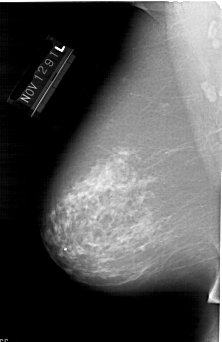

A_1648_1.LEFT_CC

LEFT_CC LINES 6871 PIXELS_PER_LINE 4141 BITS_PER_PIXEL 12 RESOLUTION 43.5 NON_OVERLAY